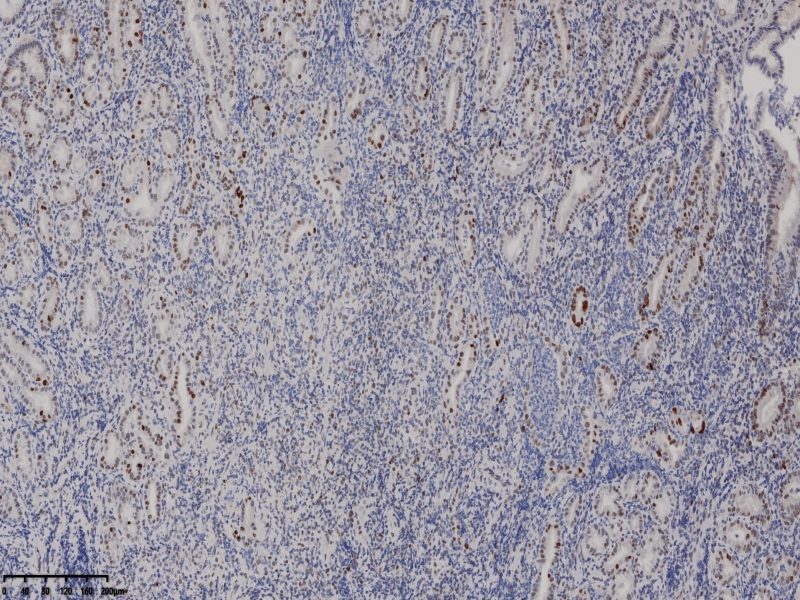

YP53

布),符合局灶黏膜内癌变(牵手癌);KI67:60%,CK7:部分+,CK20:表层腺体+,MUC5:

30%,MUC6:60%+,Villin5%,CDX-2 -,p53 60%,CEA 10%, SYN 散在+,10%;